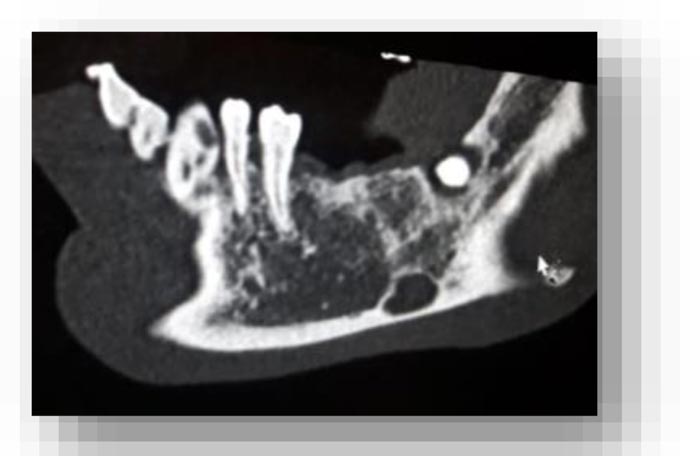

From the objective exam and the panoramic radiography, we observed the presence of multiple edentulous areas which needed to be rehabilitated. As part of an implant-prosthetic plan of care, Spiral Computerized Tomography was prescribed to him (Fig. 3), obtaining bi-dimensional reconstructions as panorex, parasagittal slices by multiplanar reformation and tridimensional reconstructions by volume rendering [12, 13].

In this radiographic exam, we found an oval notch with radiolucent, clear and regular borders, located in the inferior portion of the horizontal branch of the mandible, on the lingual side, near the angle of the mandible, and below the mandibular canal. The X-ray allowed precise measurement showing a height ranging between 13.5 mm and 17 mm and breadth between 6 and 8 mm (Figs. 4-5).

The bi-dimensional reconstructions in parasagittal slices also permitted better identification of the closeness of the bone cavity to the canal of the alveolar inferior omolateral nerve, whereas the computerized volume rendering offered a more accurate view of the surrounding anatomical features (Figs. 6-12).